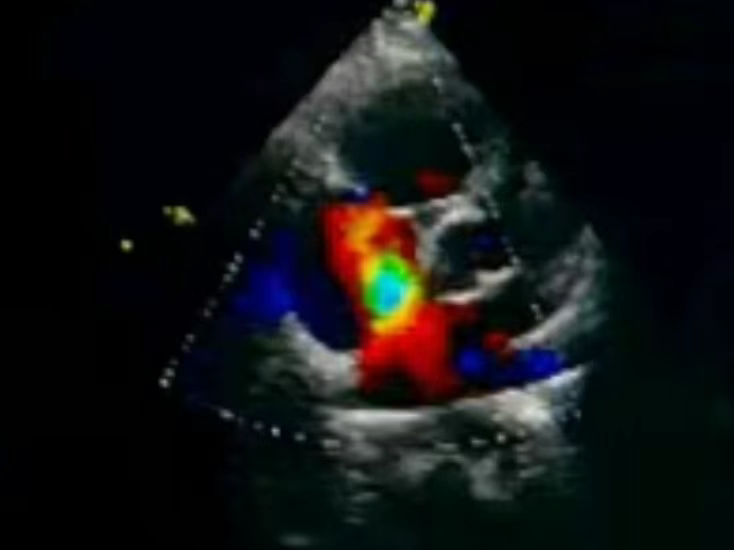

PWD、CDFI:上述房间隔中断处可见左向右分流信号。二尖瓣口血流:E/A>1;三尖瓣口收缩期见反流信号+~++,峰速2.82m/s,压差31mmHg,估测肺动脉压41mmHg。

彩色血流观察

彩色血流显示封堵成功,无残余分流